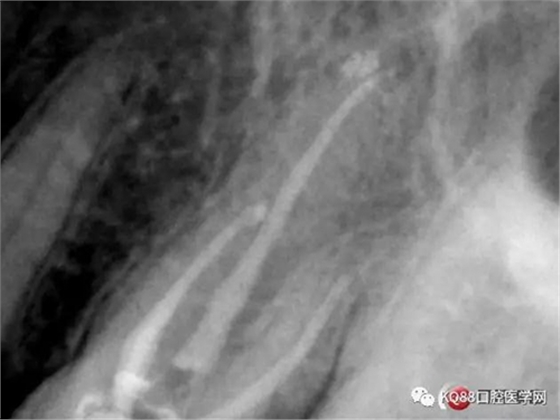

第一開髓后,只看見三個根管,于是進(jìn)行三個根管的預(yù)備,然后按照髓底解剖圖,進(jìn)行Mb2探查,近中頰根與腭根連線,遠(yuǎn)中頰根向其做垂直線,一般都在這條線附近,于是我開始去髓底白色鈣化,終于找到了Mb2,有鈣化,但是疏通后,到達(dá)根方,于是拍攝插針片。

四個根管成型,只是近中兩個根管融合為一個,典型的C型根管。最后開始根充,射片。

充填完成。以此兩例根管治療,說明的并不是完全技巧,更多的是態(tài)度,我的根管治療做的并不是很好,但是我一定會把態(tài)度端正起來,希望同行們都能一起加油,利用手上最基本的設(shè)備,用心做好每一個根管。如有錯誤,請多指證,謝謝!